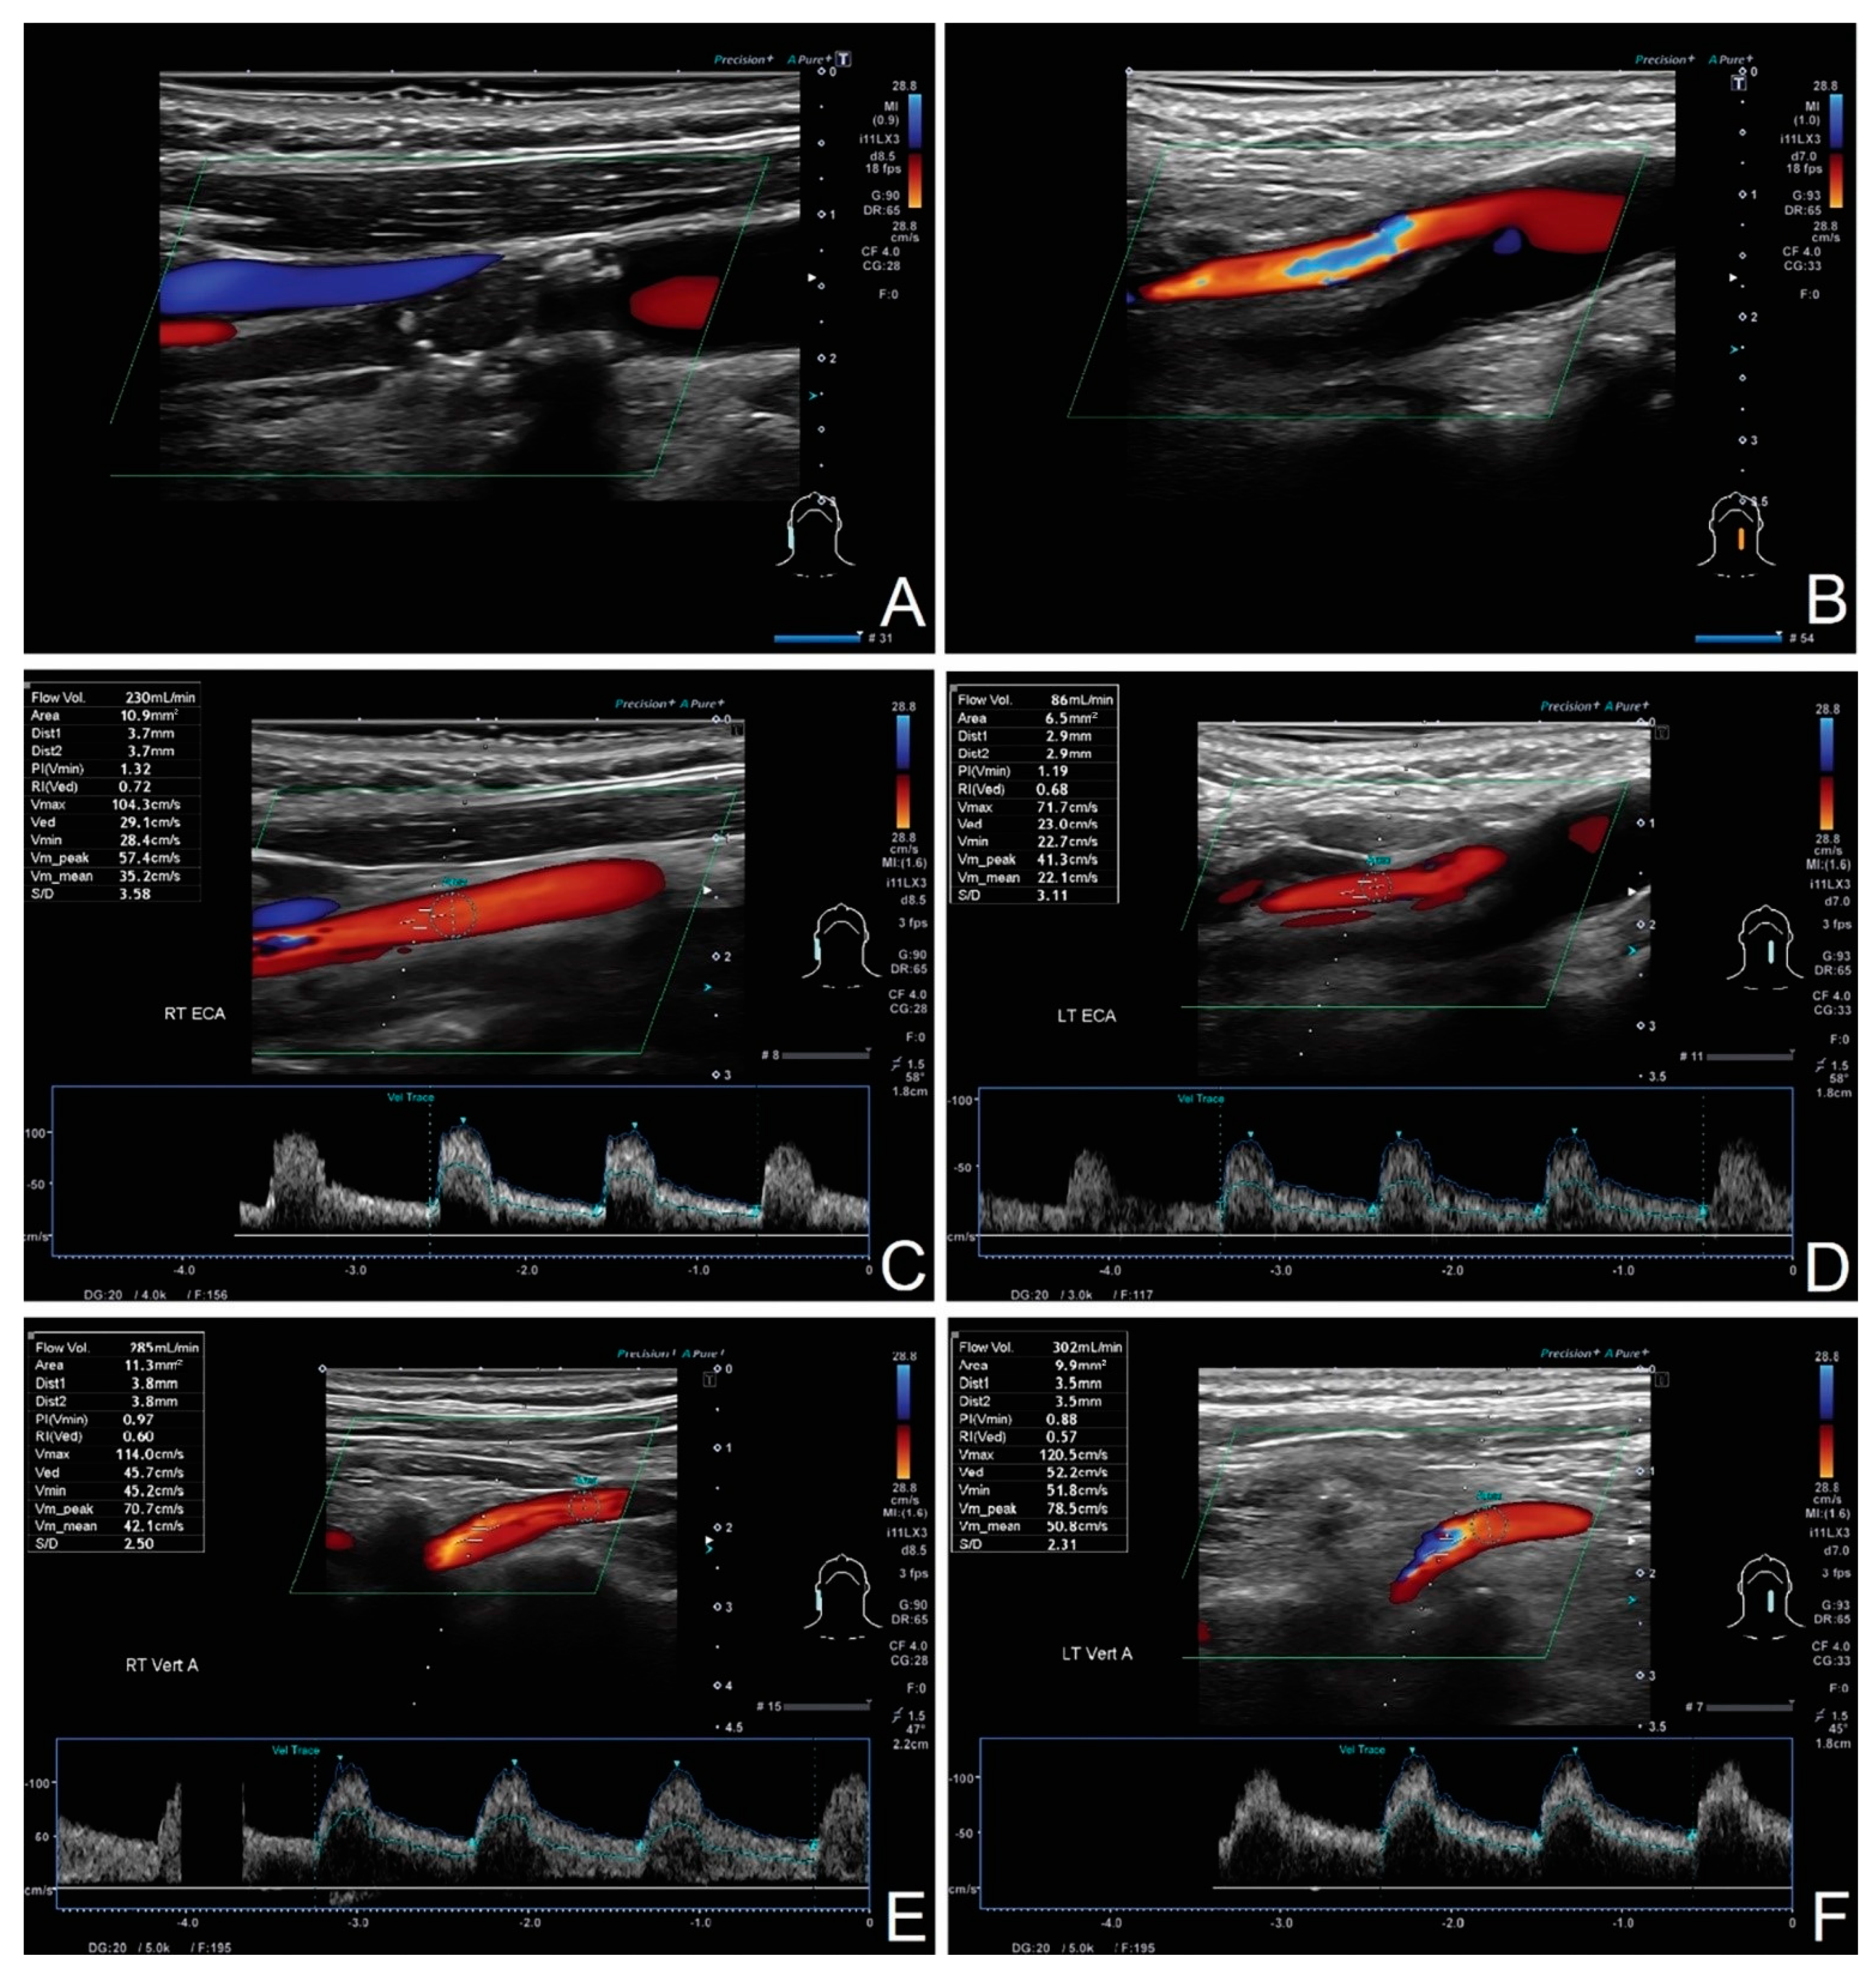

Basics Of Extracranial Carotid Artery Duplex Ultrasound Iame

Diagnostics Free Full Text Intracranial Flow Volume Estimation In Patients With Internal Carotid Artery Occlusion Html

11 Carotid Artery Stenosis Part 1 B Mode And Color Flow 123 Sonography

8 Eca Vs Ica External Versus Internal Carotid Artery 123 Sonography